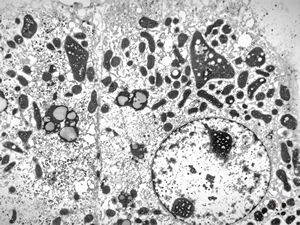

F,3m. | giant cell hepatitis - cholestasis

F,3m. | giant cell hepatitis